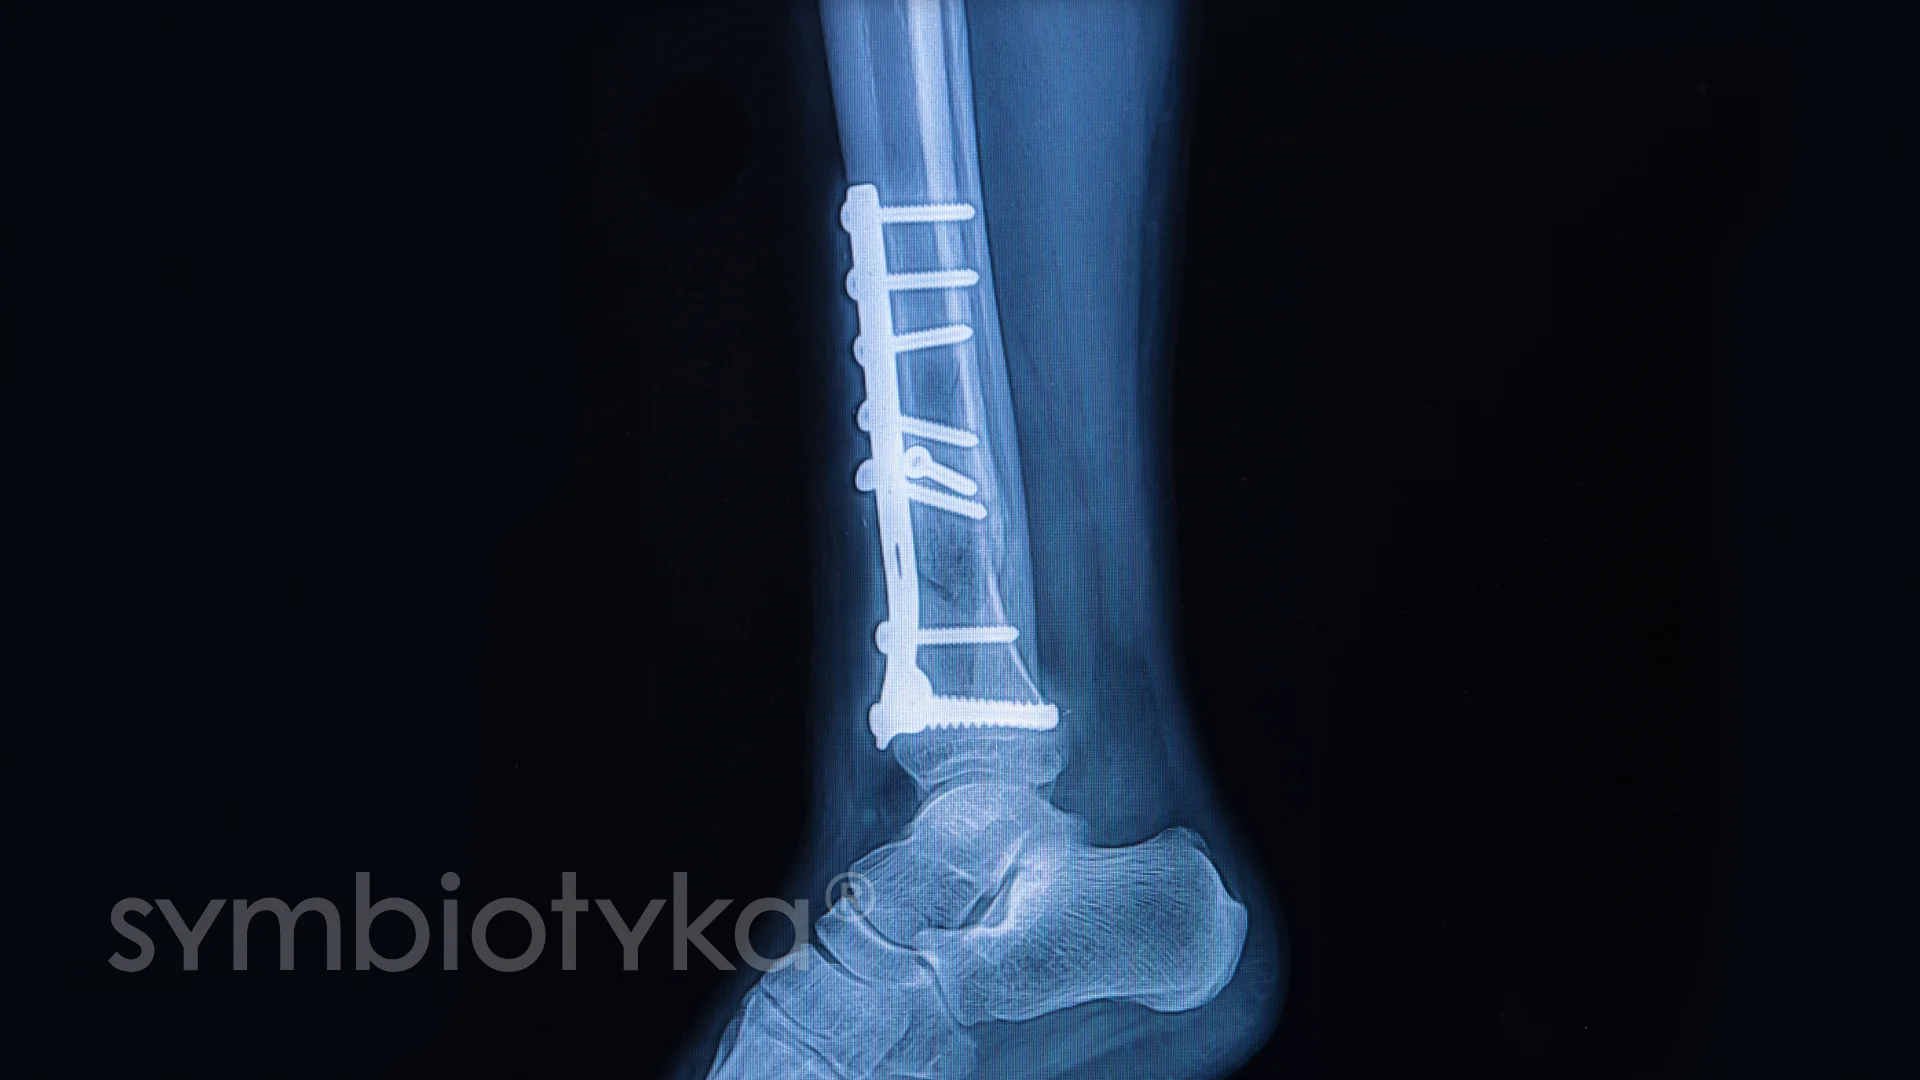

Правда в тому, що сучасні методи остеосинтезу — це щось особливе. Апарат Ілізарова, методи фіксації за допомогою пластин, гвинтів і ще чого тільки не. Дивує? Так воно і є. Інколи здається, що більше нічого не потрібно, але медичний прогрес не зупиняється.

- Використання пластин: забезпечення міцної фіксації

- Гвинти: додаткові замки для кісток